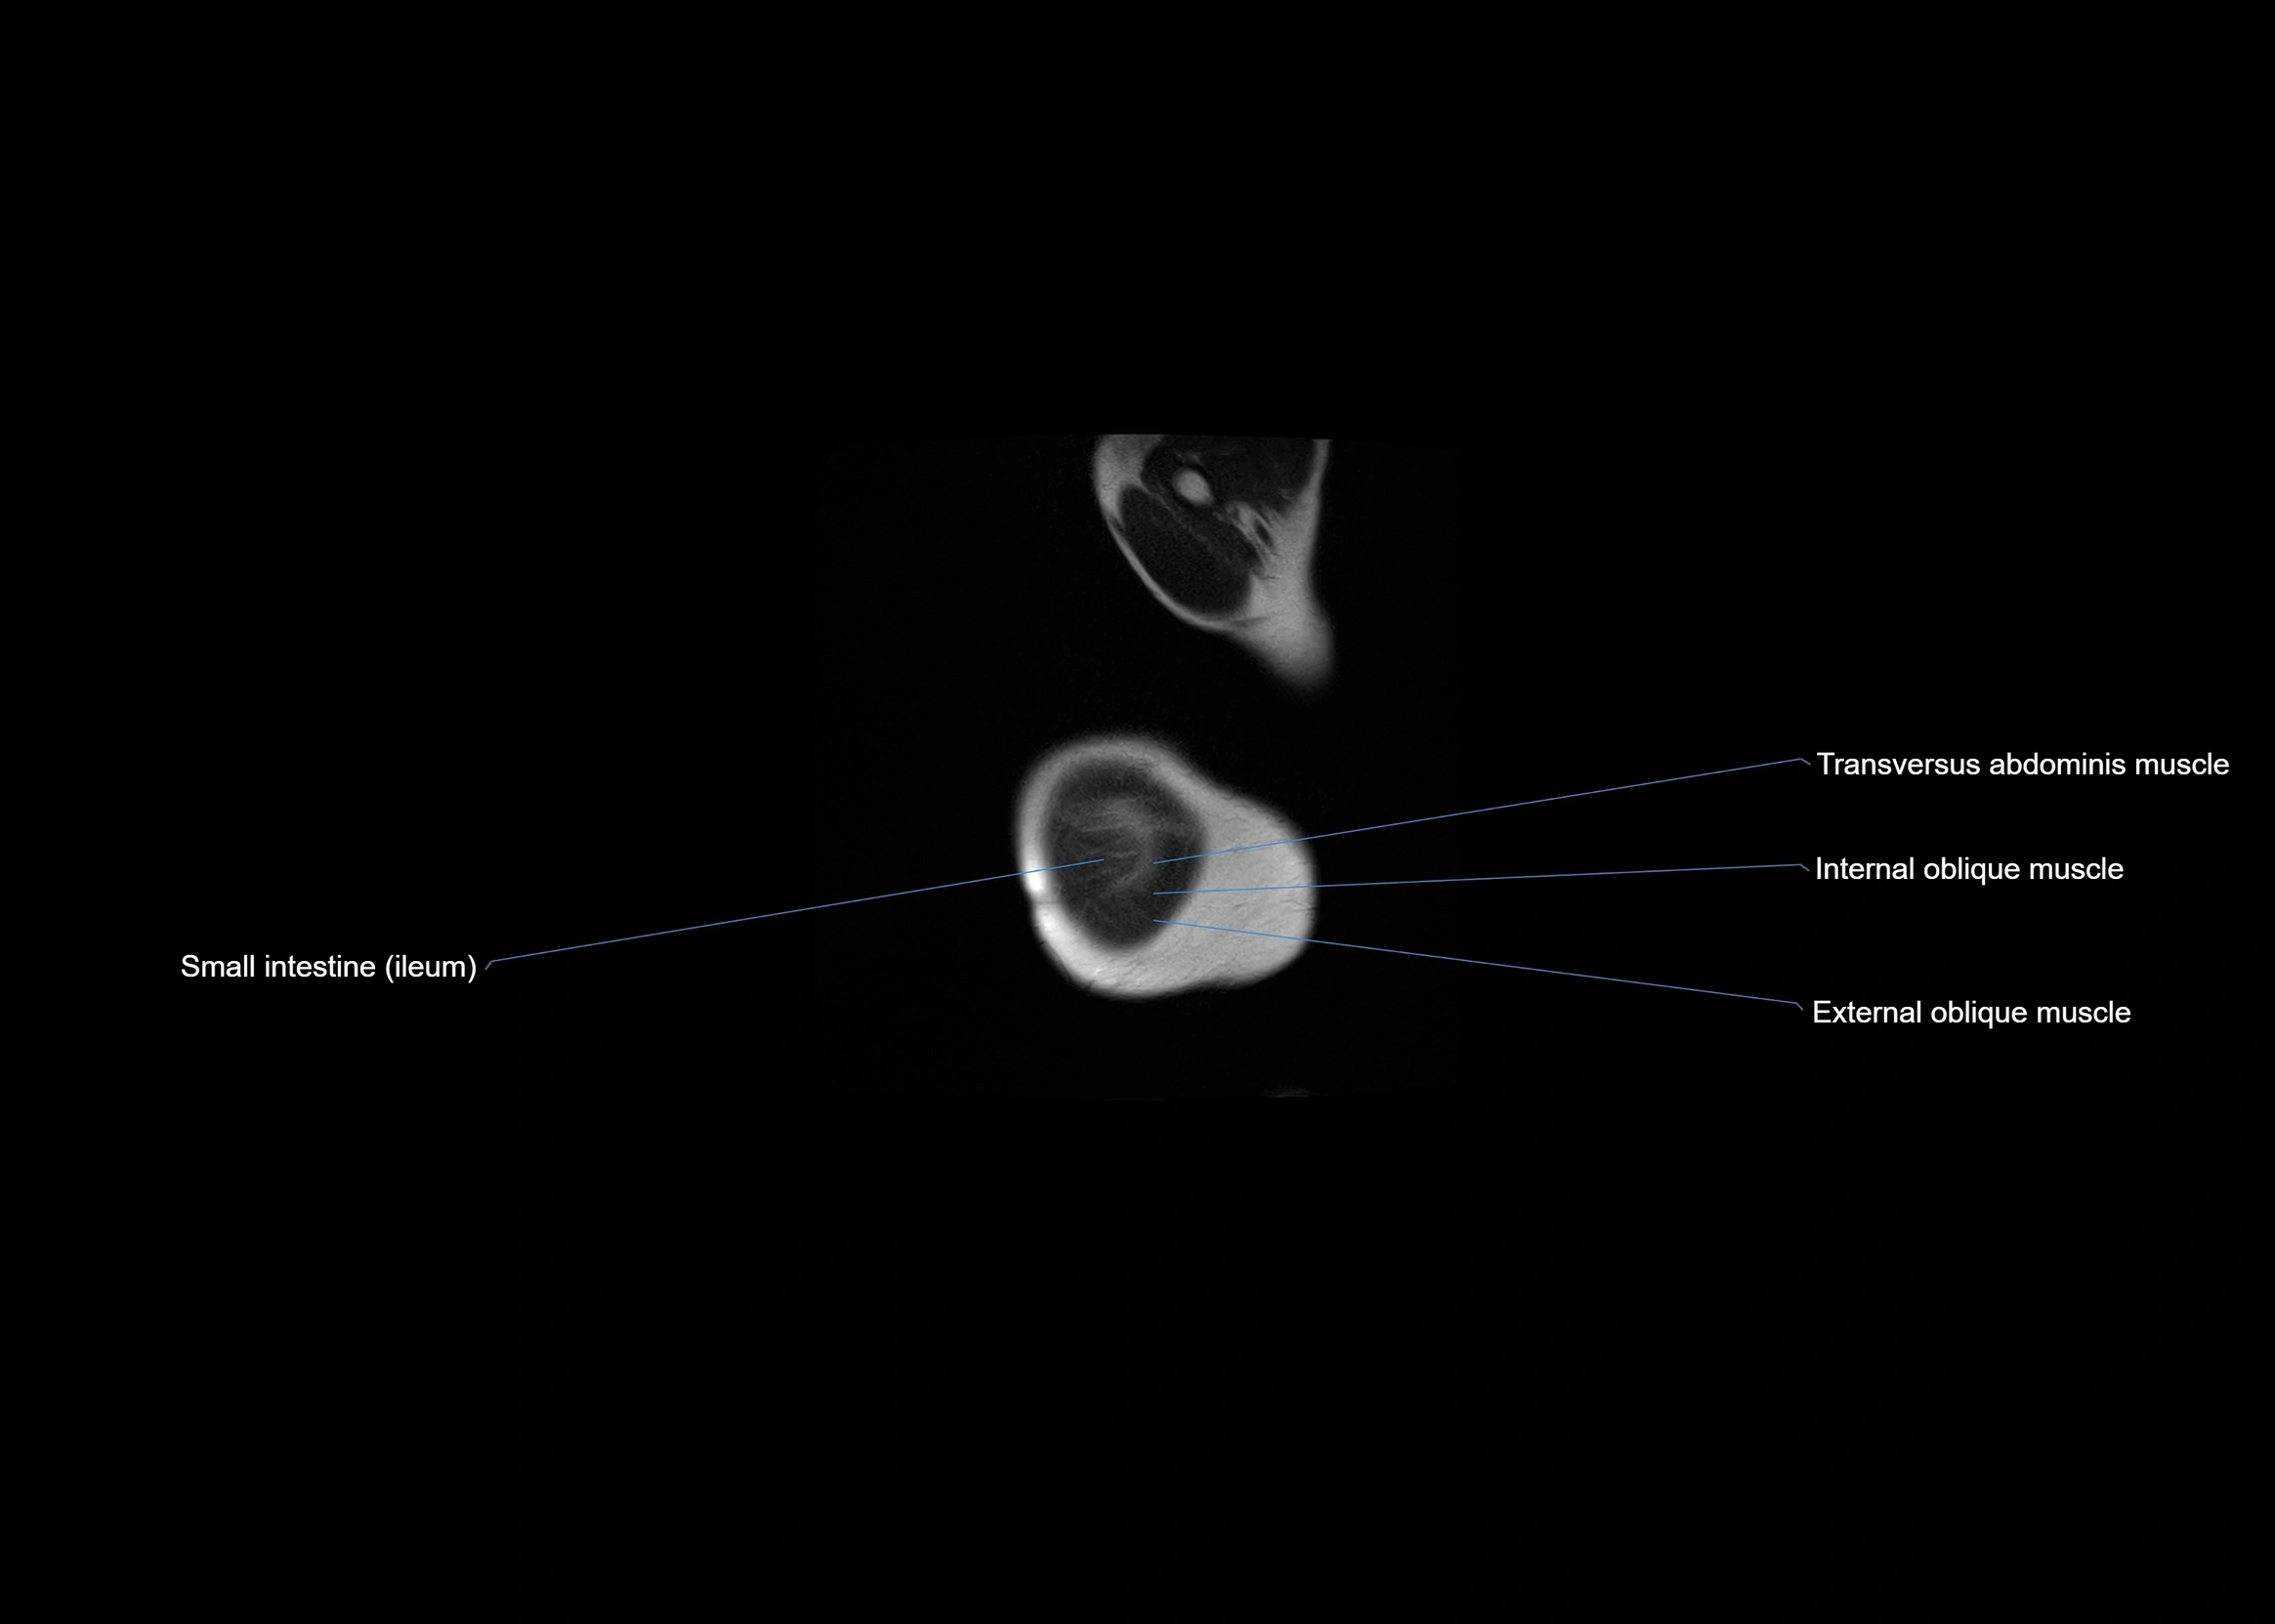

MRI images